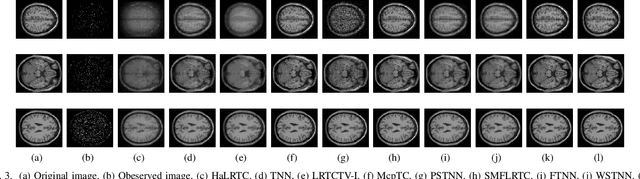

Tensor recovery is an important problem in computer vision and machine learning. It usually uses the convex relaxation of tensor rank and $l_{0}$ norm, i.e., the nuclear norm and $l_{1}$ norm respectively, to solve the problem. It is well known that convex approximations produce biased estimators. In order to overcome this problem, a corresponding non-convex regularizer has been proposed to solve it. Inspired by matrix equivalent Minimax-Concave Penalty (EMCP), we propose and prove theorems of tensor equivalent Minimax-Concave Penalty (TEMCP). The tensor equivalent MCP (TEMCP) as a non-convex regularizer and the equivalent weighted tensor $\gamma$ norm (EWTGN) which can represent the low-rank part are obtained. Both of them can realize weight adaptive. At the same time, we propose two corresponding adaptive models for two classical tensor recovery problems, low-rank tensor completion (LRTC) and tensor robust principal component analysis (TRPCA), and the optimization algorithm is based on alternating direction multiplier (ADMM). This novel iterative adaptive algorithm can produce more accurate tensor recovery effect. For the tensor completion model, multispectral image (MSI), magnetic resonance imaging (MRI) and color video (CV) data sets are considered, while for the tensor robust principal component analysis model, hyperspectral image (HSI) denoising under gaussian noise plus salt and pepper noise is considered. The proposed algorithm is superior to the state-of-arts method, and the algorithm is guaranteed to meet the reduction and convergence through experiments.